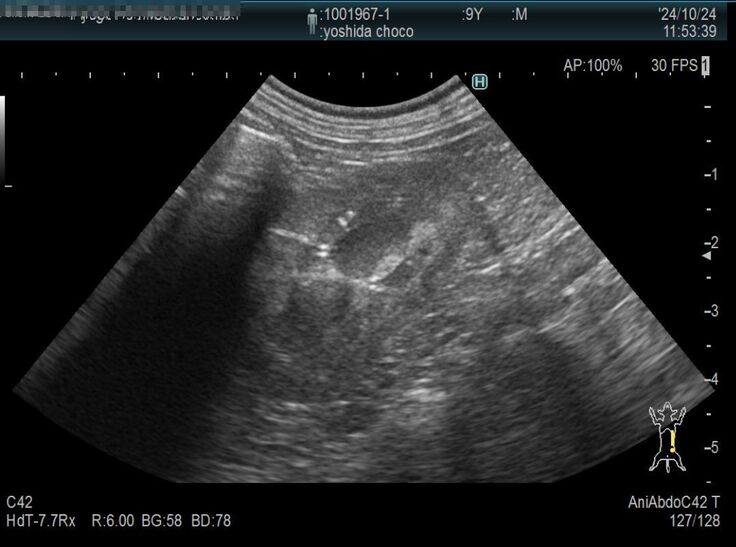

以前より下部尿路疾患で尿路結石を持っているチョコですが、膀胱にある結石が大きくなり膀胱を痛めて膀胱炎を頻繁に発症するようになりました。

膀胱炎から炎症が全身に、更には脾臓の腫瘍が確認されました。

膀胱炎の資料をご覧ください。

検査結果もかなりの異常さが分かると思います。

現在9歳のチョコですが、脾臓はいずれ摘出した方が良いと獣医師より指摘されております。まだ若いので悪性の可能性は低いと言われています。また、結石も同時に摘出をした方が良いと。

検査の結果、脾臓肥大が限界近くの爆発寸前になっていることが判明しました。

脾臓は4センチまでなってるから、いつ破裂してもおかしくない状況。